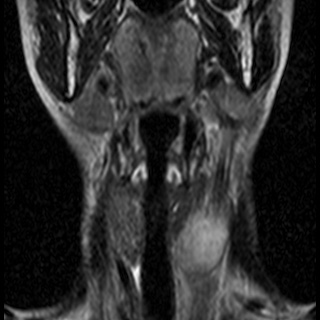

Невринома множественная шейного отдела с врастанием в спинно-мозговой канал

Здравствуйте! Мне 27 лет. Я стала жаловаться на головокружение, головные боли, пульсирование в голове. После исследования мрт выявилась следующая патология . Документы предоставляю. Можете ли Вы помочь в этой патологии? Как попасть к Вам на консультацию, учитывая эпидемиологическую обстановку? Спасибо.